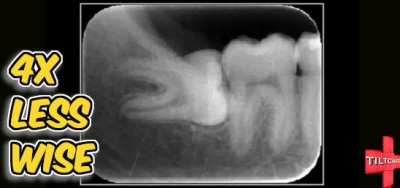

S16 EP 630 4X Less Wise

It's the last episode of Season 16!  We are changing the format up so this is the last long form episode for a while.  This week we discuss the bigger games we have been exploring as well as a full review of Death Stranding 2 and our initial thoughts of Silksong.  Tune in! Episode